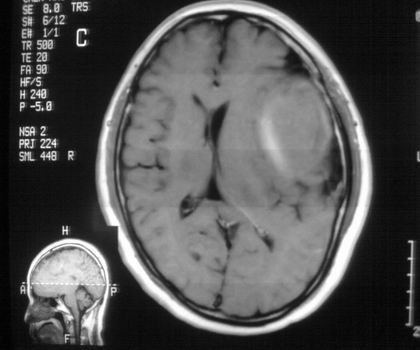

以下是引用影像孺子牛在2008-4-29 21:20:00的发言:[br]首先病变定位在脑外,根据ct密度及mri信号特征考虑慢性硬膜下血肿不连续环形钙化。

以下是引用周战梅在2008-4-29 23:12:00的发言:[br]脑外病变,蛛网膜下腔增宽,囊壁点状、环形钙化,增强扫描呈不均匀环状强化,考虑为囊性脑膜瘤可能性大,慢性脓肿、血肿机化、胆脂瘤不能除外。